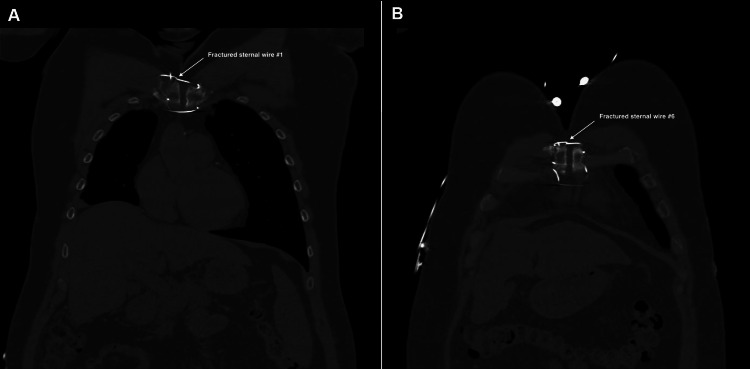

Before assessment in our outpatient clinic, the patient underwent a chest X-ray, as well as CT and echocardiography imaging for structural and functional evaluation. X-ray and CT chest imaging (Figures 1–2) revealed probable chronic non-union of the sternum with no evidence of dense bony bridging across the sternum. There was no evidence of any acute or concerning abnormalities in the anterior mediastinum or definite acute abnormalities in the chest. The imaging also showed that wires number one (Figure 2A) and six (Figure 2B) were broken.

Video 1 shows a transverse view of the chest CT imaging, demonstrating the full-length chronic sternal non-union, as well as the fractured wires one and six.

Following a standard institutional timeout, the patient underwent a redo full median sternotomy to address a sternal non-union. Upon opening, the surgical team found no signs of infection but discovered the first and sixth sternal wires to be broken, and the left and right top Robicsek wires to be loose, as had been indicated by the preoperative CT scan. The sternum was also found to be unstable. Firstly, the original sternal wires were therefore removed (Figure 3).